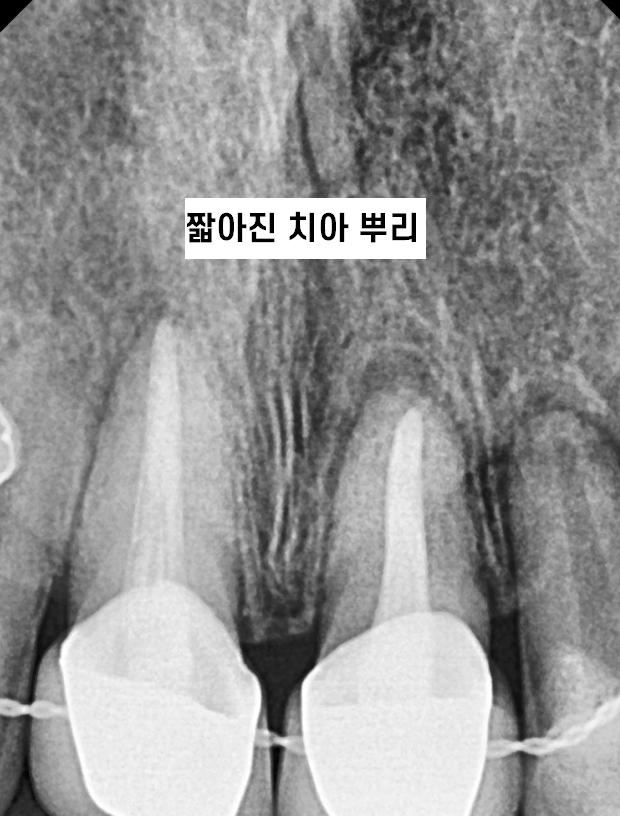

- 치근 흡수

치근 흡수란 교정 과정에서 치아 뿌리가 점차 짧아지는 현상입니다.

치근 = 치아 뿌리를 뜻하는데요.

치아 뿌리가 짧을 수록 치아의 수명이 단축된답니다.

(흔들리기 쉬우니까요~)

반대로 치아 뿌리가 길면 튼튼하고요!!

치아 교정은 치아 뿌리를 이동하는 것인데

과도한 힘이 가해질 경우 발생할 가능성이 높습니다.

때문에 적절한 힘을 조절하면서 교정하여야하고

정기적인 x-ray 촬영을 통해 치아 뿌리를 항상 확인해주어야한답니다!